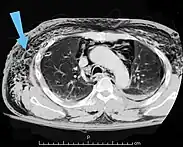

Scanner abdominal (rayons X) d'un patient présentant un emphysème sous-cutané (flèché) | |

Les cas importants d'emphysème sous-cutané sont faciles à diagnostiquer en raison des signes caractéristiques de l'affection. Dans certains cas, les signes sont subtils, ce qui rend le diagnostic plus difficile. L'imagerie médicale est utilisée pour diagnostiquer la maladie ou confirmer un diagnostic établi à l'aide de signes cliniques. Sur une radiographie du thorax, l'emphysème sous-cutané peut être vu comme des stries radiotransparentes dans le modèle attendu du groupe de muscles principaux du pectoral. L'air présent dans les tissus sous-cutanés peut interférer avec la radiographie du thorax, ce qui peut masquer des affections graves comme le pneumothorax. Elle peut également réduire l'efficacité de l'échographie thoracique. D'autre part, comme l'emphysème sous-cutané peut être visible sur les radiographies du thorax avant un pneumothorax, sa présence peut être utilisée pour déduire celle de cette dernière lésion. L'emphysème sous-cutané peut également être observé sur les scanners, les poches d'air apparaissant comme des zones sombres. Le scanner est si sensible qu'il permet généralement de trouver l'endroit exact d'où l'air pénètre dans les tissus mous. En 1994, M. T. Macklin et C. C. Macklin ont publié d'autres aperçus sur la physiopathologie du syndrome de Macklin spontané survenant à la suite d'une grave crise d'asthme. La présence d'un emphysème sous-cutané chez une personne qui semble très malade et fébrile après une crise de vomissements suivie d'une douleur thoracique gauche est très évocatrice du diagnostic du syndrome de Boerhaave, qui est une urgence vitale causée par une rupture de l'œsophage distal. L'emphysème sous-cutané peut être une complication de l'insufflation de CO2 avec la chirurgie laparoscopique. Une augmentation soudaine du CO2 en fin de marée après la hausse initiale qui se produit avec l'insufflation (les 15-30 premières minutes) devrait faire suspecter un emphysème sous-cutané. Il est à noter que l'oxymétrie de pouls et la pression des voies aériennes ne varient pas dans l'emphysème sous-cutané, contrairement à l'intubation endobronchique, au capnothorax, au pneumothorax ou à l'embolie au CO2.